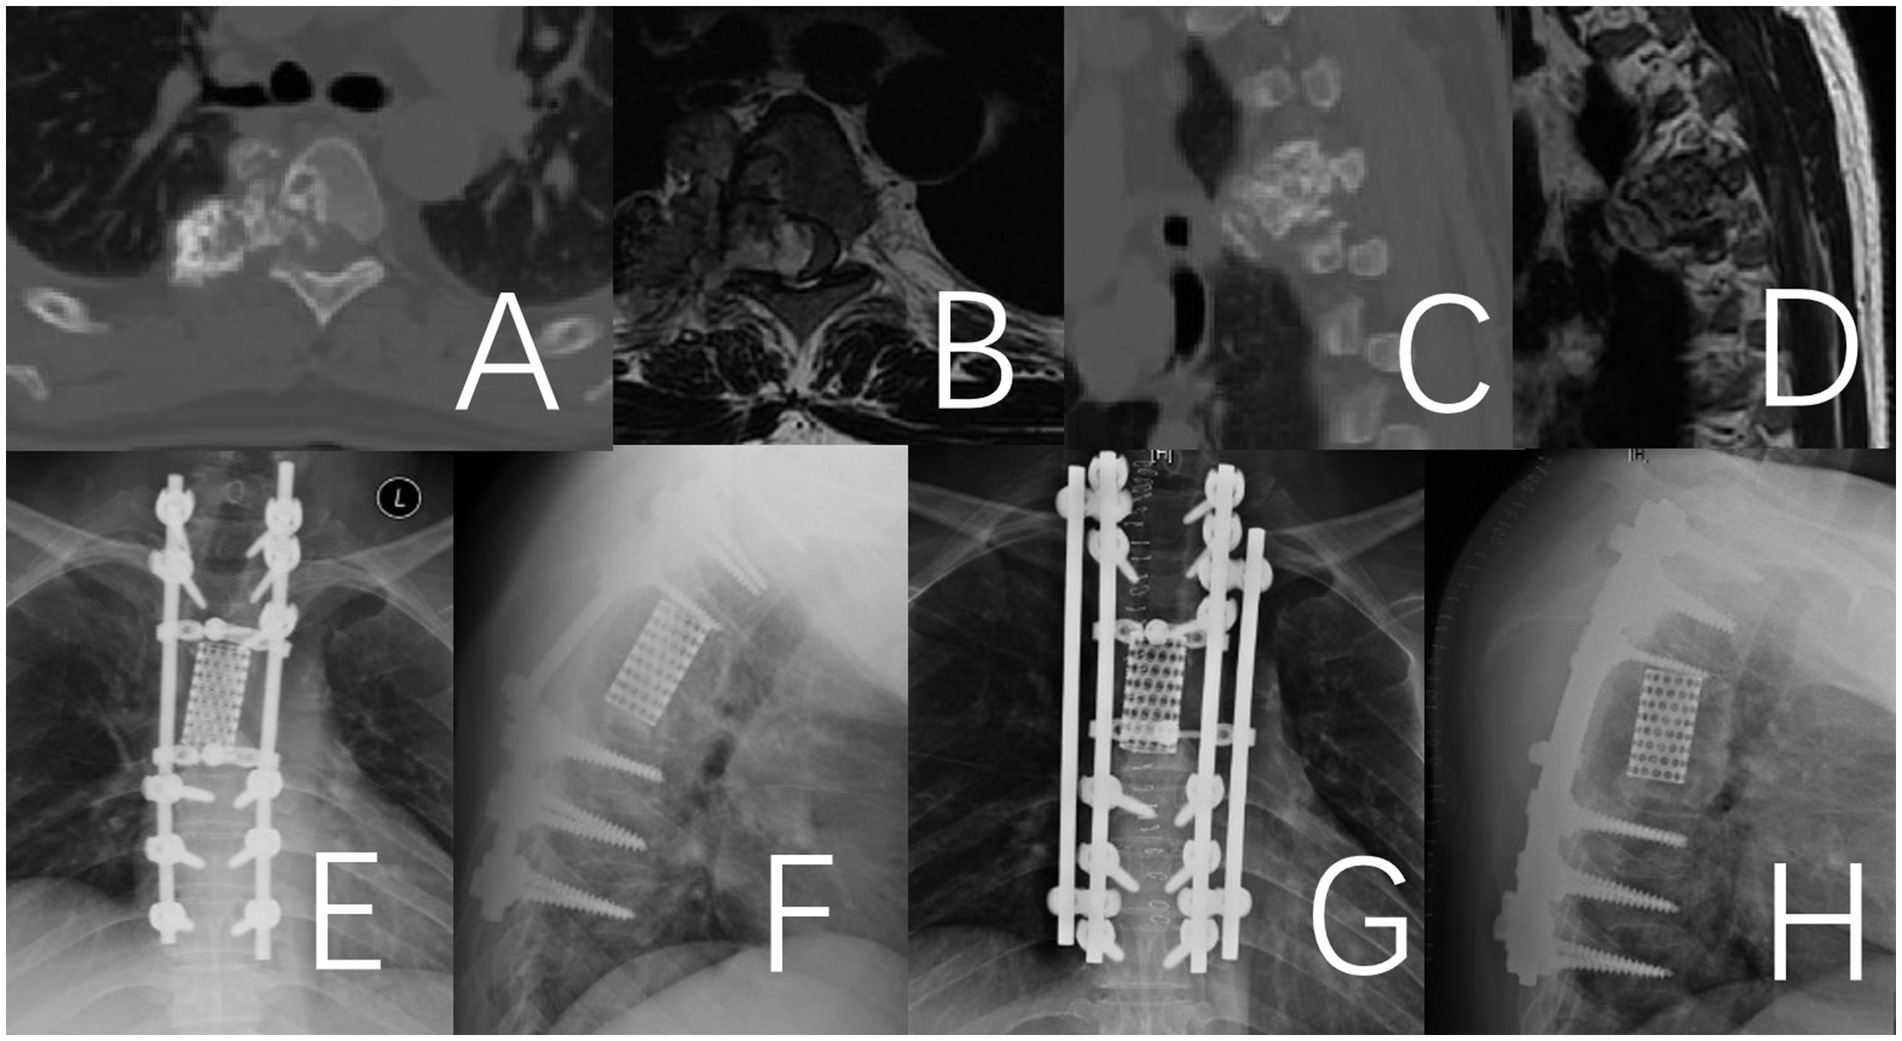

Two patients experienced hardware failures within 26 and 38 months postoperatively, characterized by fractures in the titanium fixation rods, which necessitated revision surgery (Figures 4, 5). Both patients who experienced hardware failure had undergone initial reconstruction with titanium mesh. In contrast, no fixation failure was observed in patients who received a 3D-printed vertebral body for reconstruction.

Figure 4. Fracture of the titanium rod observed 38 months after the operation in a 41-year-old male patient with thoracic chondrosarcoma. (A–D) Preoperative CT and MRI. (E,F) Depict the fractured titanium rod. (G,H) Illustrate the internal fixation after revision surgery.

Figure 5. Fracture of the titanium rod observed 26 months after the operation in a 49-year-old male patient with thoracic giant cell tumor. (A–D) Preoperative CT and MRI. (E,F) Depict the fractured titanium rod. (G,H) Illustrate the internal fixation after revision surgery.